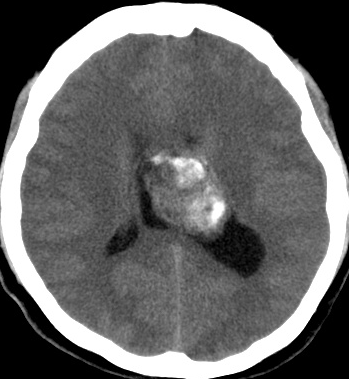

無症状で見つかった小さいcentral neurocytomaのCT像です

incidental tumor 偶発腫といいます。病理診断はないのですが,まず間違いなくcentral neurocytomaで,数年間の観察で全く増大しませんでした。高齢の患者さんでは無症候で発見し,経過を見ていくと嚢胞変性を来たし,自然退縮していくものも見られす。この例でも,左のモンロー孔は閉塞していて,左側脳室は水頭症となっていますが,無症候です。おそらくこの腫瘍は今後も症候性となることはありません。センロラルニューロサイトーマは,神経鞘腫と同様に加齢によって変性し退縮する自然歴を有している腫瘍です。